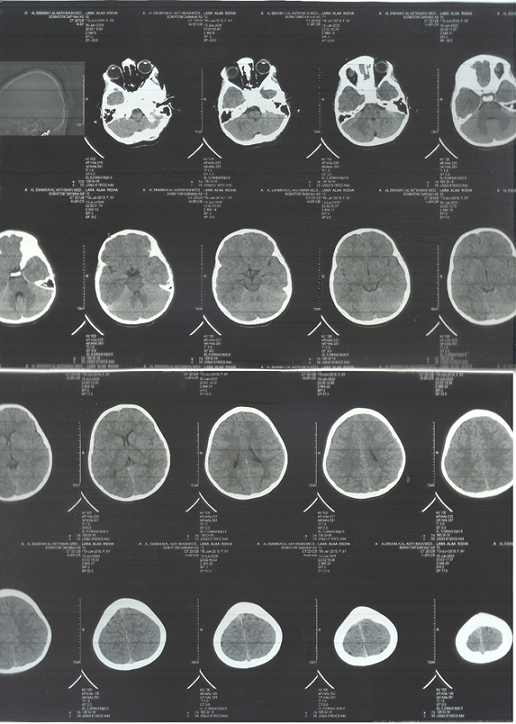

A non-contrast CT brain scan (Figure-2) revealed asymmetric cortical atrophy predominantly in the left posterior frontal and parietal lobes, particularly affecting the perisylvian region. The sulci appeared widened and the underlying white matter volume reduced. There were no calcifications or signs of progressive degenerative disease.

Main brain CT-scan findings Abnormal Findings:

1. Asymmetry of Cortical and White Matter Volumes (Suggestive of Focal Cortical Atrophy)

There is evident left cerebral hemisphere volume loss, especially in the left posterior frontal and parietal lobes, as seen by widened sulci and dilated cortical subarachnoid spaces.

The left lateral ventricle appears slightly enlarged compared to the right (ex-vacuo dilatation), which supports underlying parenchymal volume loss on the left side. This asymmetry is subtle but clear across multiple slices.

2. Subtle Cortical Dysgenesis or Malacia

In the affected left hemisphere, particularly the posterior regions, there appears to be poor differentiation between the gray and white matter, which may reflect focal cortical dysplasia or encephalomalacia. This pattern matches well with focal seizure onset zones in pediatric epileptics.

Figure-2A

Figure-2B

Brain imaging revealed left-sided cortical atrophy, particularly involving the perisylvian and temporoparietal regions.

The left posterior frontal-parietal cortical atrophy, visible on CT, is in a region crucial for language, social cognition, and motor planning. This could explain the patient’s autistic features.

The focal cortical atrophy noted in the left perisylvian and temporoparietal cortex suggests a congenital or early-acquired static lesion, such as focal cortical dysplasia or sequela of perinatal injury. These regions are critical for language and social cognition, and their dysfunction could underlie both autistic and epileptic manifestations.